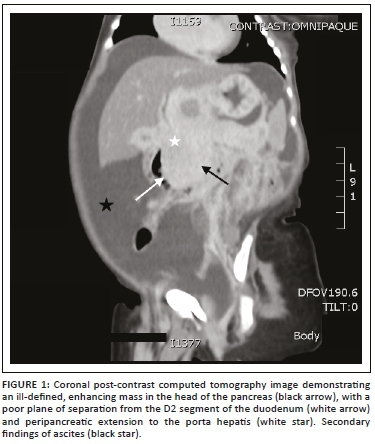

This was followed by a computed tomography (CT) scan of the abdomen and pelvis with an intravenous and oral contrast agent. Computed tomography imaging showed an ill-defined, enhancing mass in the head of the pancreas (Figures 1-3), with a poor plane of separation from the D2 segment of the duodenum (Figures 1 and 3). Enhancing soft tissue, which extended beyond the confines of the pancreatic head into the region of the porta hepatis, was also noted and appeared to be contiguous with this mass (Figure 1).

The differential diagnosis based on the imaging studies was that of a pancreatic vascular neoplasm; however, with the laboratory evidence of Kasabach-Merritt phenomenon (KMP), this prompted the diagnosis of a pancreatic KHE. Given the large size and peripancreatic extension of this lesion, a differential diagnosis of pancreaticoblastoma was considered; however, these lesions are typically heterogeneous in appearance with both cystic and solid components and often have calcifications.

On ultrasound, KHE appears as a homogeneous, ill-defined, soft tissue mass, which may be isoechoeic or hyperechoic compared to the pancreas, with associated mild to marked increased vascularity on colour Doppler.2,6 All previously reported cases described a mass in the head of the pancreas, as in this case report.6 Although the possibility of a vascular tumour could be suggested on US, a more specific diagnosis cannot be made because of the limitations in demonstrating the infiltrative portions and exact extent of KHE. Computed tomography and MRI together with magnetic resonance cholangiopancreatography (MRCP) are of added value in localising the mass, assessing the tumour extent and giving information of any associated findings such as dilation of the pancreatic and biliary ducts, duodenal obstruction and ascites. Leung et al. presented a case of a pancreatic KHE presenting with neonatal duodenal obstruction.1